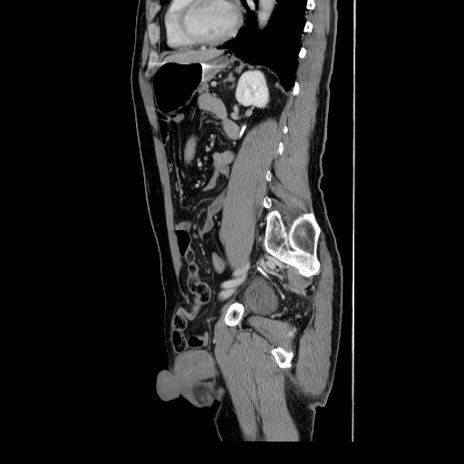

横断像

【症例】60歳代 男性

【主訴】右鼠径部膨隆

【現病歴】1年程前より右鼠径部膨隆あり。自己にて還納可能だったため放置していた。3時間前より右鼠径部の脱出を認め、還納困難となり受診。

【身体所見】右鼠径部に小児頭大の膨隆あり。弾性硬であり、用手還納は困難。左鼠径部にも膨隆を認める。脱出はなし。